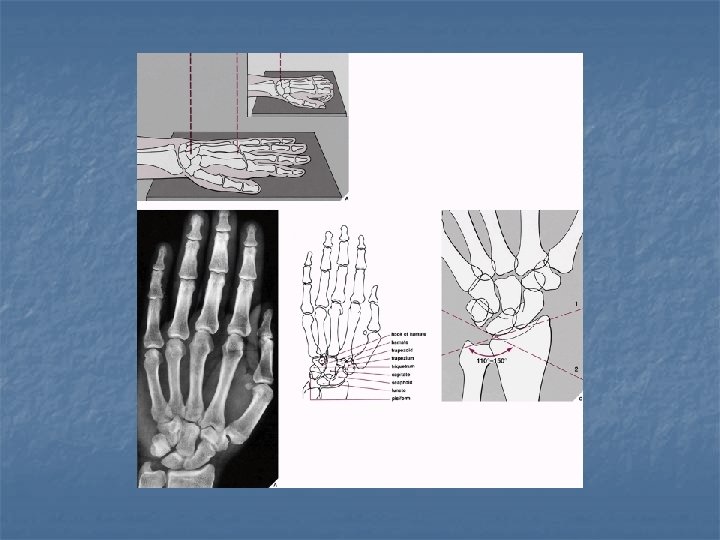

Radiographic views n n n Dorsovolar (PA) Lateral Dorsovolar with ulnar deviation (scaphoid) Supinated oblique (pisiform, pisotriquetral joint) Pronated oblique (triquetral) Carpal tunnel (hook of hamate, pisiform, volar trapezium)

Dorsovolar with ulnar deviation

Supinated oblique

Pronated oblique view

Carpal Tunnel view

Normal anatomical relations n Lateral view with wrist in neutral position: radius, lunate, capitate, 3 rd metacarpal should be in the same line.

Normal anatomical relations n Dorsovolar view with wrist in neutral postion: 3 smooth unbroken arcs should be seen (Gilula arcs) Arc I: proximal articular surfaces of the scaphoid, lunate, & triquetrum n Arc II: distal concavities of scaphoid, lunate, & triquetrum n Arc III: proximal convexities of capitate & hamate n